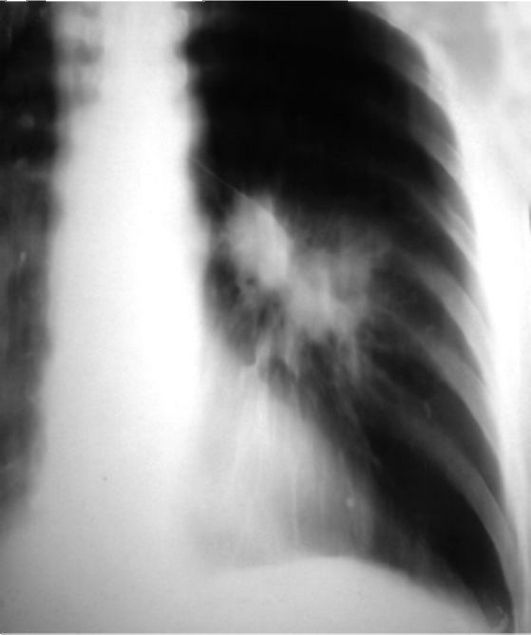

Пациент Б., 61 год.

Рентгенограммы органов грудной полости в прямой и левой боковой проекциях.

Слева в обнаруживается тень неправильной гантелеобразной формы, размерами 4x6 см, состоящая как бы из нескольких слившихся узлов, с неровными бугристыми и лучистыми контурами. От тени к корню видна «дорожка». Левый корень структурен, расширен за счёт двух круглых теней, диаметром 1,5 см, которые образуют полицикличность наружного контура корня. На остальном протяжении левое и правое лёгкие прозрачны, лёгочный рисунок не изменён. Правый корень не расширен, структурен. Тень средостения обычного расположения, несколько расширена за счёт левого желудочка сердца, аорта имеет обычное расположение и диаметр, уплотнена. В плевральной полости жидкость не определяется. Диафрагма расположена на уровне VI ребра, форма её куполообразная.

Заключение: периферический рак левого лёгкого в S, осложнённый метастазами в лимфатические узлы корня. Для уточнения параметров опухоли рекомендуется рентгеновская томография органов грудной полости.

Рис. 3.10. Пациент Б., 61 год. Рентгеновская томограмма органов грудной полости в прямой проекции левого лёгкого на глубине 6 см.

Периферический рак левого лёг- кого в SVI